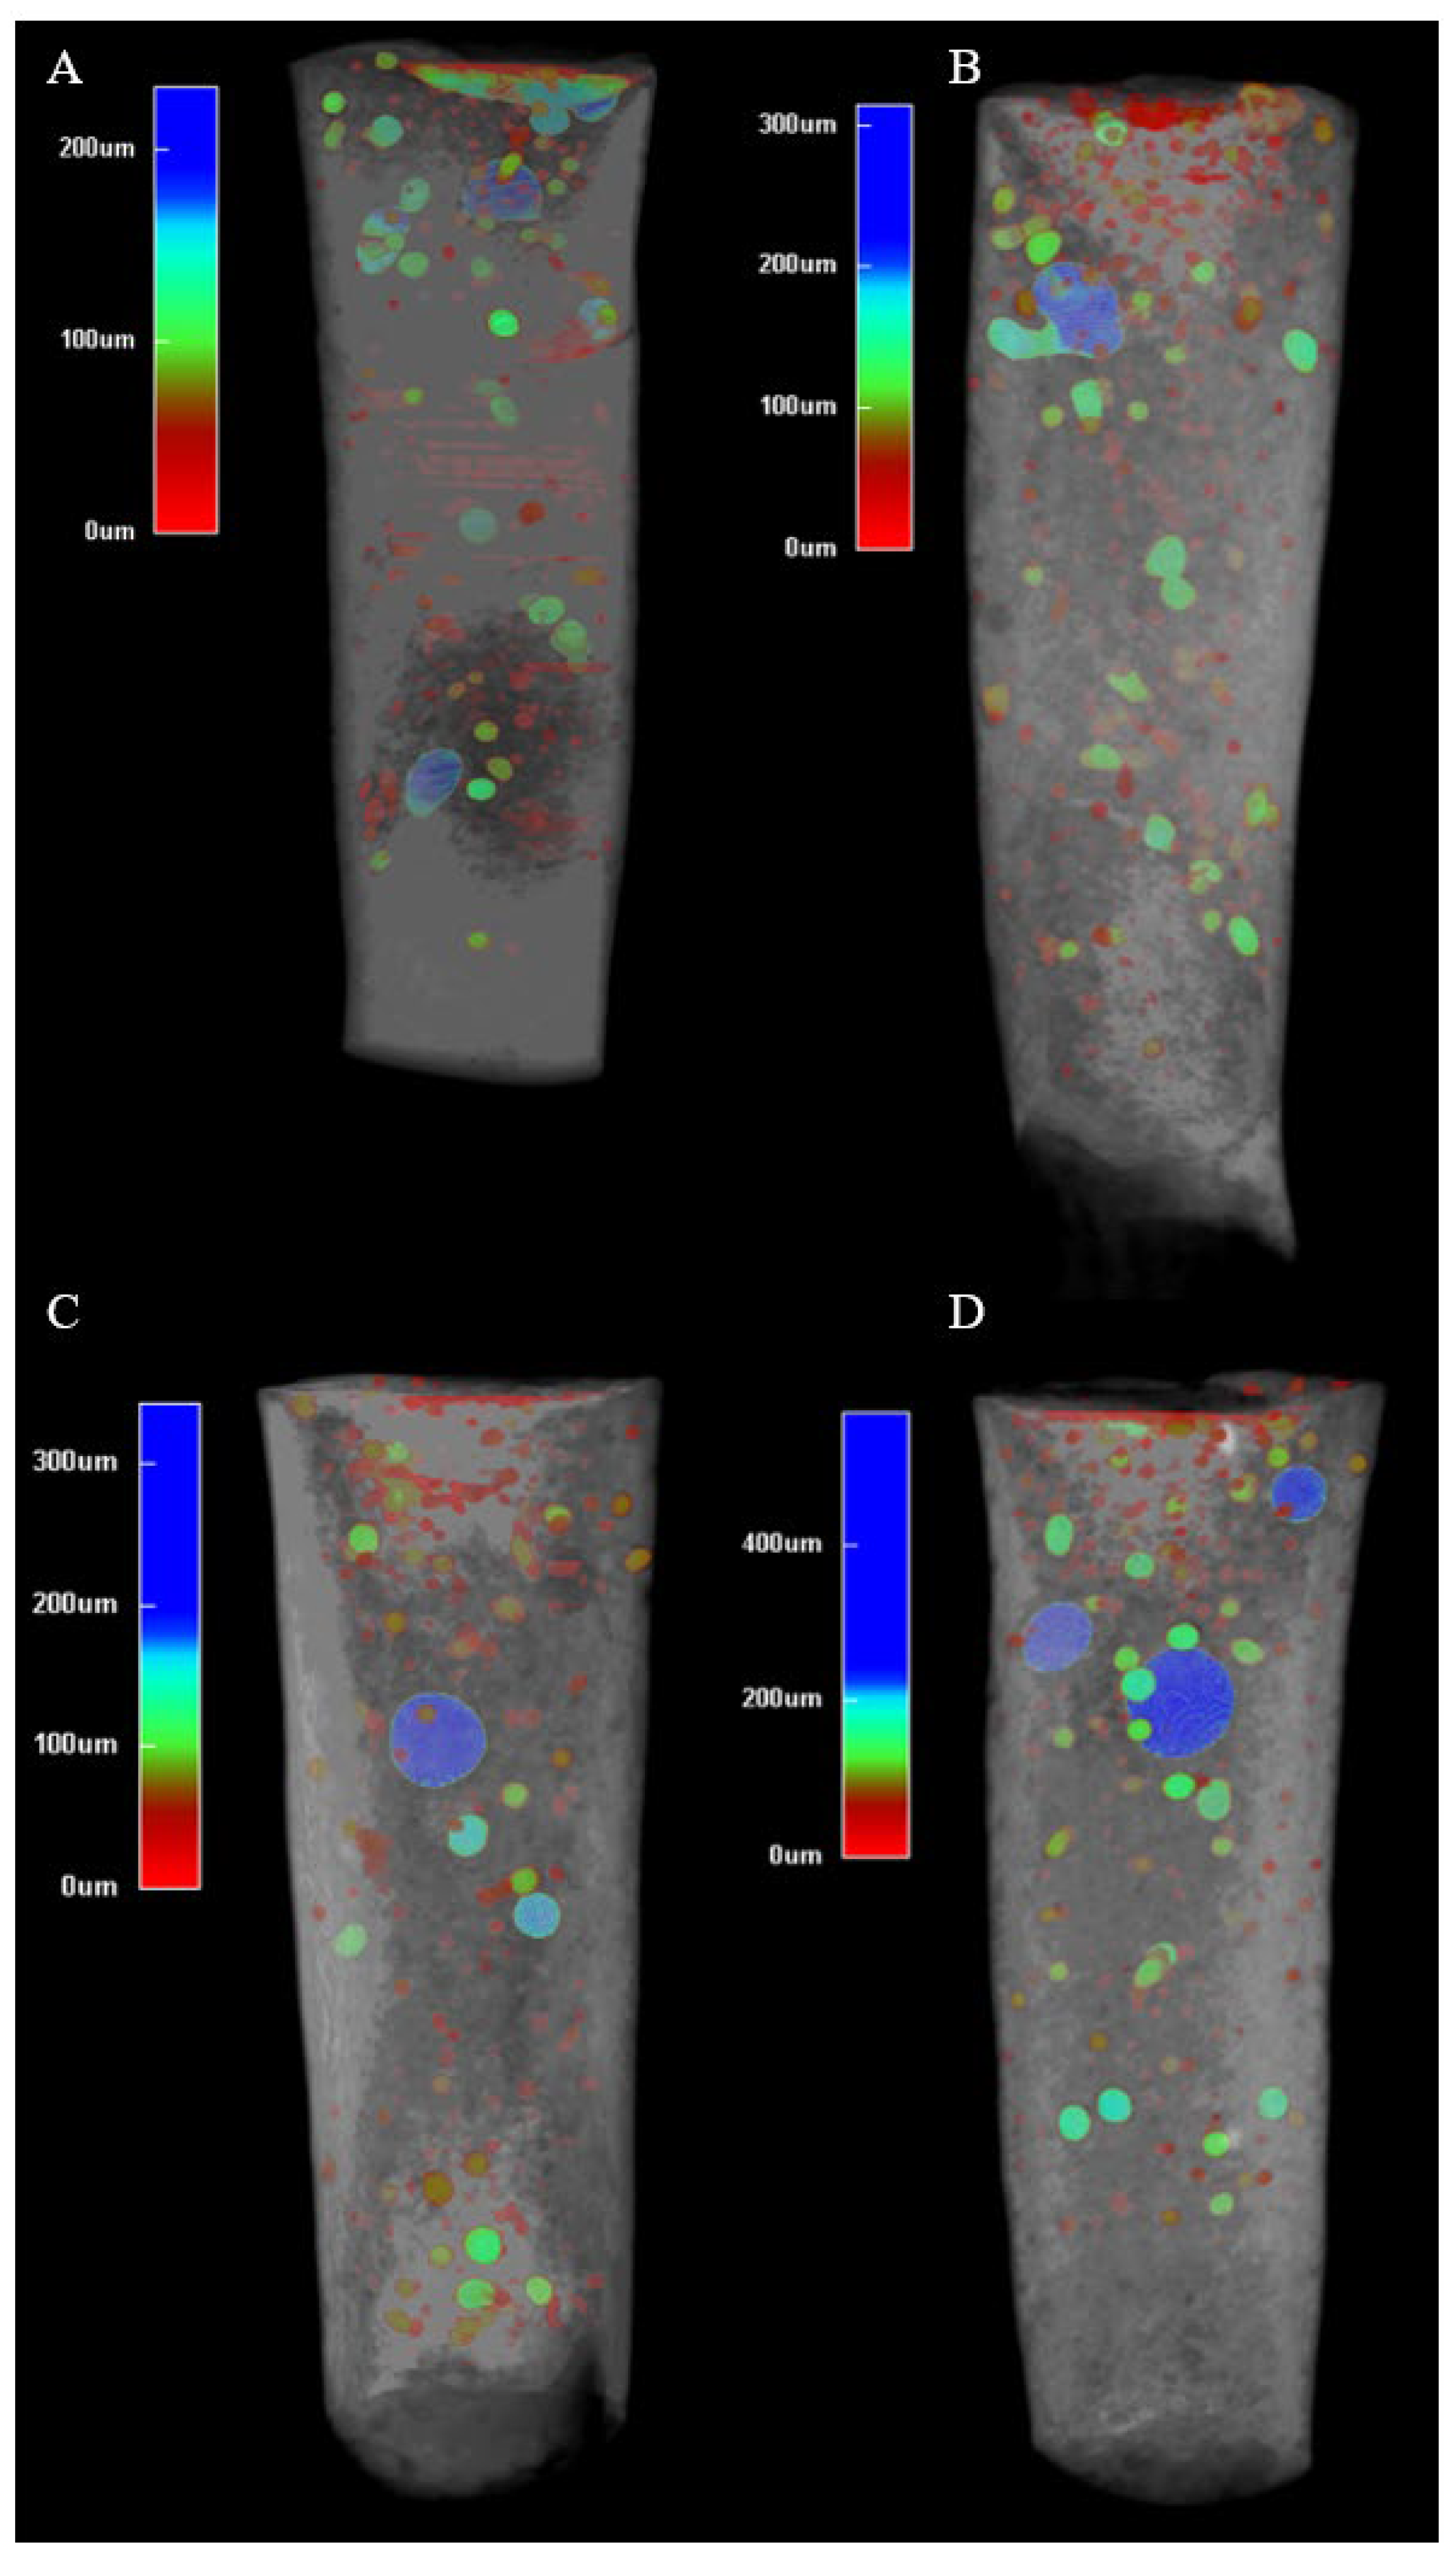

13]. The consistent internal microstructure across all groups (

Figure 3) suggests that Well-Root™ PT’s premixed formulation ensures uniform hydration, likely due to its optimized viscosity and reduced technique sensitivity compared to manually mixed materials like MTA [

13,

15]. Clinically, increased external voids with prolonged activation may weaken the apical seal, elevating the risk of microleakage and bacterial infiltration, which could lead to periapical inflammation or treatment failure [

24]. Conversely, the lower void volumes and higher microhardness achieved with 3 s activation (

Figure 3 and

Figure 4) support a denser, more durable apical barrier, enhancing the long-term prognosis of endodontically treated immature permanent teeth. These findings underscore the importance of optimizing ultrasonic activation duration to balance material compaction with marginal adaptation, ensuring effective sealing and mechanical stability.

41]. This study shows that no placement technique is currently able to create void-free apical plugs (

Figure 2). Brief ultrasonic activation for 3 s minimizes void formation and maintains higher microhardness compared to longer durations of 9 and 15 s. Specifically, 15 s ultrasound condensation resulted in significantly higher external and total void volumes (

p < 0.001), suggesting that prolonged ultrasonic activation may disrupt the material’s homogeneity and its adaptation to dentin walls. This aligns with previous research, which reported that excessive ultrasonication (beyond 10 s) increases porosity and void formation in calcium silicate-based materials, such as mineral trioxide aggregate (MTA), due to over-vibration and potential microcavitation effects [